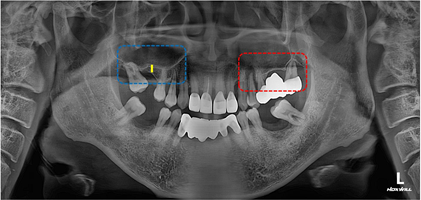

빨간색 : 보철 후 앞니가 벌어짐

노란색: 치조골이 녹아서 잇몸상태가 좋지 않음

파란색: 발치 후 방치하여 어금니가 쓰러짐

두번째 문제인 어금니로 넘어가보겠습니다.

어금니의 경우 두가지 문제가 있는데요.

첫째로 어금니들이 쓰러져있다는 것

둘째로 위턱뼈가 모자라다는 것